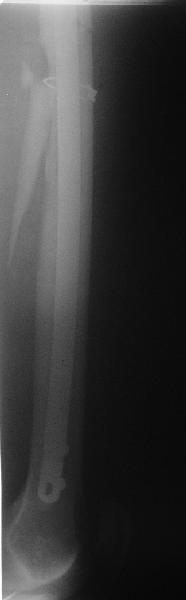

Пациент попал под наше наблюдение через 3 недели после первого остеосинтеза (фото 1). Учитывая, нестабильность остеосинтеза, выстоящий стержень закрыто перештифтовали (фото 2), через 3 месяца динамизация. К 5 месяцам имели укорочение 2 см, при том, что динамический винт стал статическим. От дальнейшей динамизации отказались, учитывая наличие контакта между фрагментами и возможность прогрессирования укорочения. К 1,5 года сращение не достигнуто (фото 3). Удалили гвоздь, выполнили дистракционный остеосинтез с целью стимуляции остеогенеза и компенсации укорочения (фото 4), потом закрыто перештифтовали после рассверливания (фото 5). На сегодняшний день, через 4 месяца после последней операции (фото 6) признаков регенерата нет, длина восстановлена, ходит без дополнительной опоры.